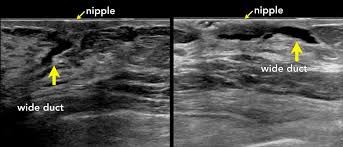

On ultrasound it will be hypoechoic with spiculations radiating away from the nipple. Radiographic features ultrasound malignant characteristics (with positive predictive values) Ultrasound imaging allows better evaluation of the status of the axillary lymph nodes in patients with ibc, an important step in determining extent of disease prior to initiation of chemotherapy. Is the abnormal enlargement of rudimentary male breast tissue. You might get a breast ultrasound: Breast cancer is among the most common causes of cancer deaths today, coming fifth after lung, stomach, liver and colon cancers. Many cancers are not visible on ultrasound. Breast cancer usually makes or presents as a mass or tumor or a lump. This type of cancer also changes the appearance of your breasts. Papillary dcis, a special variant, will show up as matter within the ducts, like a clog within a pipe. It is the most common cause of cancer death in women. in 2005 alone, 519 000 deaths were recorded due to breast cancer. this means that one in every 100 deaths worldwide and almost one in every 15 cancer deaths were due to breast cancer. Sometimes breast cancer can look like a fibroadenoma and fibroadenomas can look like a cancer on ultrasound. Many calcifications seen on mammography cannot be seen on ultrasound.

You might not need any further tests if everything looks normal. It can help your healthcare provider find breast problems. When is breast ultrasound used? If your breast tissue is too dense for a mammogram. This test is often used when a change has been seen on a mammogram or when a change is felt. Papillary dcis, a special variant, will show up as matter within the ducts, like a clog within a pipe. You may notice dimpling or pitting, and the skin on your breast. On ultrasound, a breast cancer tumor is often seen as hypoechoic, has irregular borders, and may appear spiculated. This breast cancer ultrasound image shows changes related to breast cancer that are not seen as microcalcifications or a mass or lump. Some early breast cancers only show up as calcifications on mammography. If a solid lump shows on the scan you might need to have. A rash isn't the only visual symptom of inflammatory breast cancer. Ultrasound is frequently used to evaluate breast abnormalities that are found with screening mammography or diagnostic mammography or during a physician performed clinical breast exam.ultrasound allows significant freedom in obtaining images of the.

On ultrasound it will be hypoechoic with spiculations radiating away from the nipple.